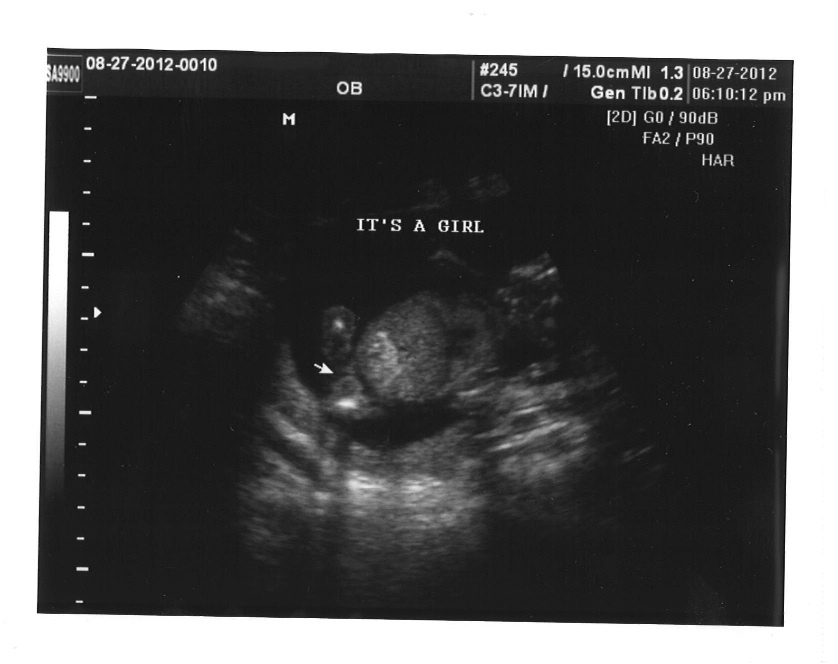

But it's confirmed ladies, IT'S A GIRL!!!!!!! :running:

There were three lines the whole time... nothing between her little legs!

Attachment 4278